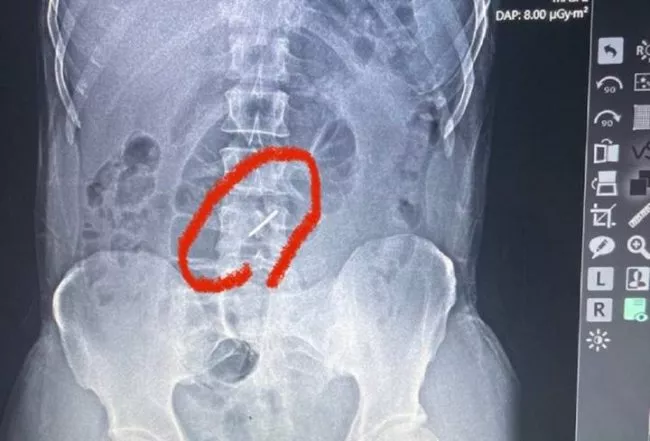

Боєць з Володимира Ігор Скучинський втратив на війні ногу, отримавши внаслідок боїв на Миколаївщині сильне поранення. Чоловік переніс дев'ять операцій, дві клінічні смерті, часткову ампутацію лівої ноги. Ще 18 уламків снаряда залишились у тілі. Попри все це боєць продовжує нести військову службу. Свою історію ...